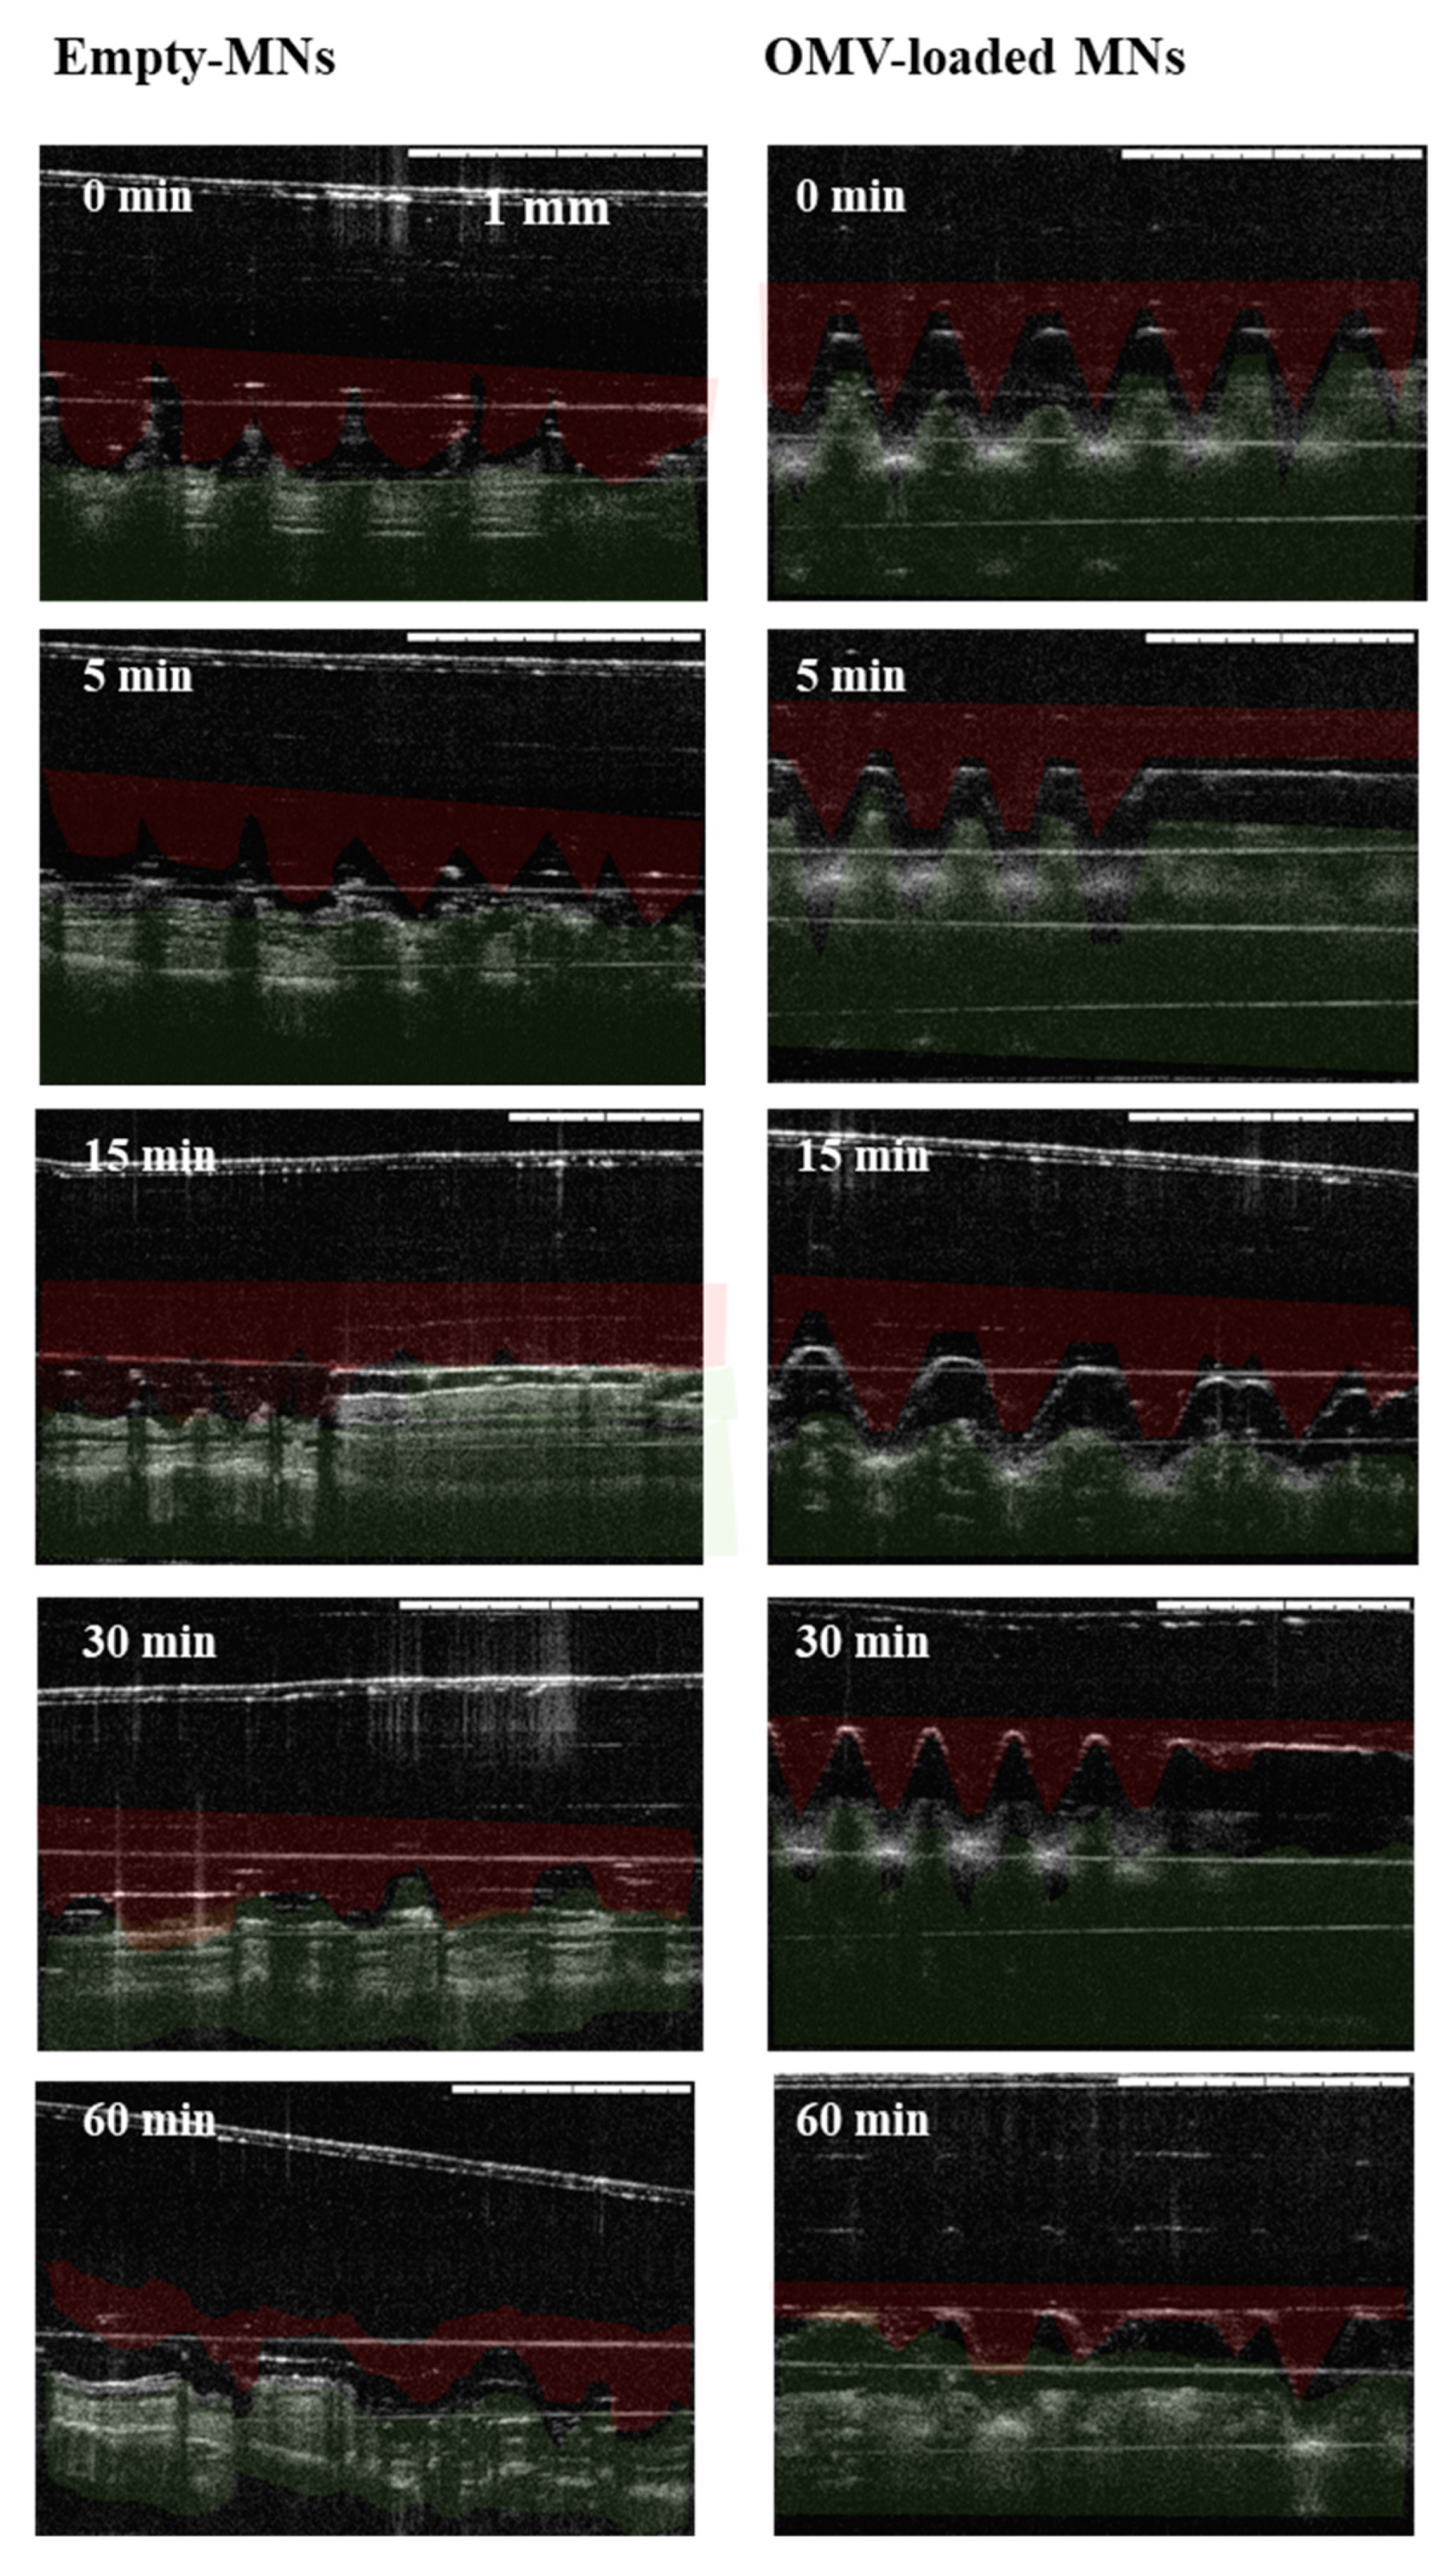

3.3.1. Insertion in Pig Skin

3.3.2. Insertion in Mice Skin